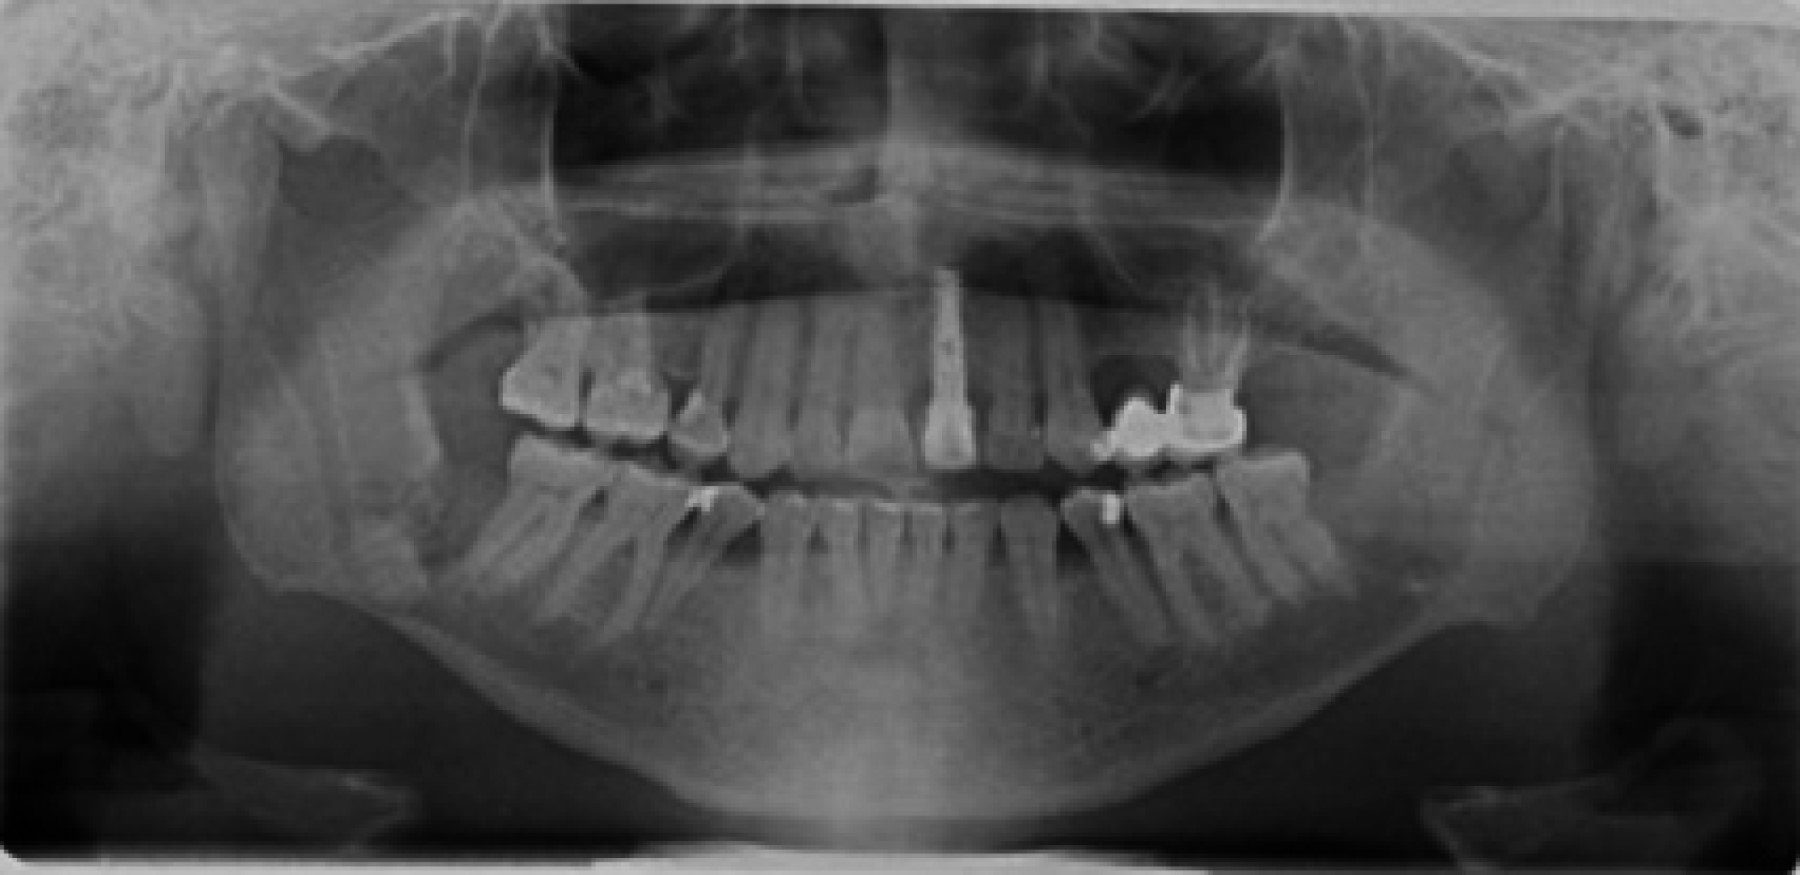

Se trata de paciente masculino de 54 años de edad y procedente de Caracas, Venezuela, quien refiere inicio de enfermedad actual en enero de 2023 posterior a ser intervenido quirúrgicamente para odontectomía de OD 4.8, en vista de presentar aumento de volumen en región paramandibular derecha, concomitante fuerte sintomatología dolorosa, acude a consulta. Al examen clínico maxilofacial, se observa asimetría facial a expensas de tercio inferior facial por aumento de volumen que involucra la región paramandibular derecha, indurado, doloroso a la palpación superficial y profunda, sin signos de flogosis. Al examen intraoral, se evidencia apertura oral disminuida, cuantificada en 15 mm, dentición permanente, oclusión estable. Alveolo de OD 4.8, en proceso de cicatrización, con capa de fibrina perialveolar, sin presencia de gasto purulento o signos de infección. Se indica ortopantomografía (Figura 1), la cual se recibe de mediana calidad técnica, donde se puede observar una imagen radiopaca en región basal de cuerpo mandibular derecho, compatible con resto radicular de OD 4.8, así como también una imagen radiolúcida sugestiva de lecho quirúrgico de odontectomía del mismo. Como hallazgo radiográfico, se puede evidenciar una imagen radiolúcida, multilobular, de bordes difusos, en región de cuerpo y ángulo mandibular izquierdo, por lo que se indica tomografía computarizada de haz cónico (Figura 2), donde en sus cortes axiales, coronales y sagitales se puede evidenciar una imagen isodensa de 4 × 3 × 2 cm multilobulada, de bordes bien definidos, con expansión de las corticales óseas en la región de cuerpo y ángulo mandibular izquierdo, en relación con los OD 3.6, 3.7. Asimismo, se observa una imagen hiperdensa en región de cuerpo mandibular derecho, compatible con resto radicular de OD 4.8. Se decide realizar intervención quirúrgica bajo anestesia local, para realizar toma de biopsia incisional en región de ángulo mandibular izquierdo, la cual reporta como resultado histopatológico: queratoquiste odontogénico (Figura 3).

Figura 1